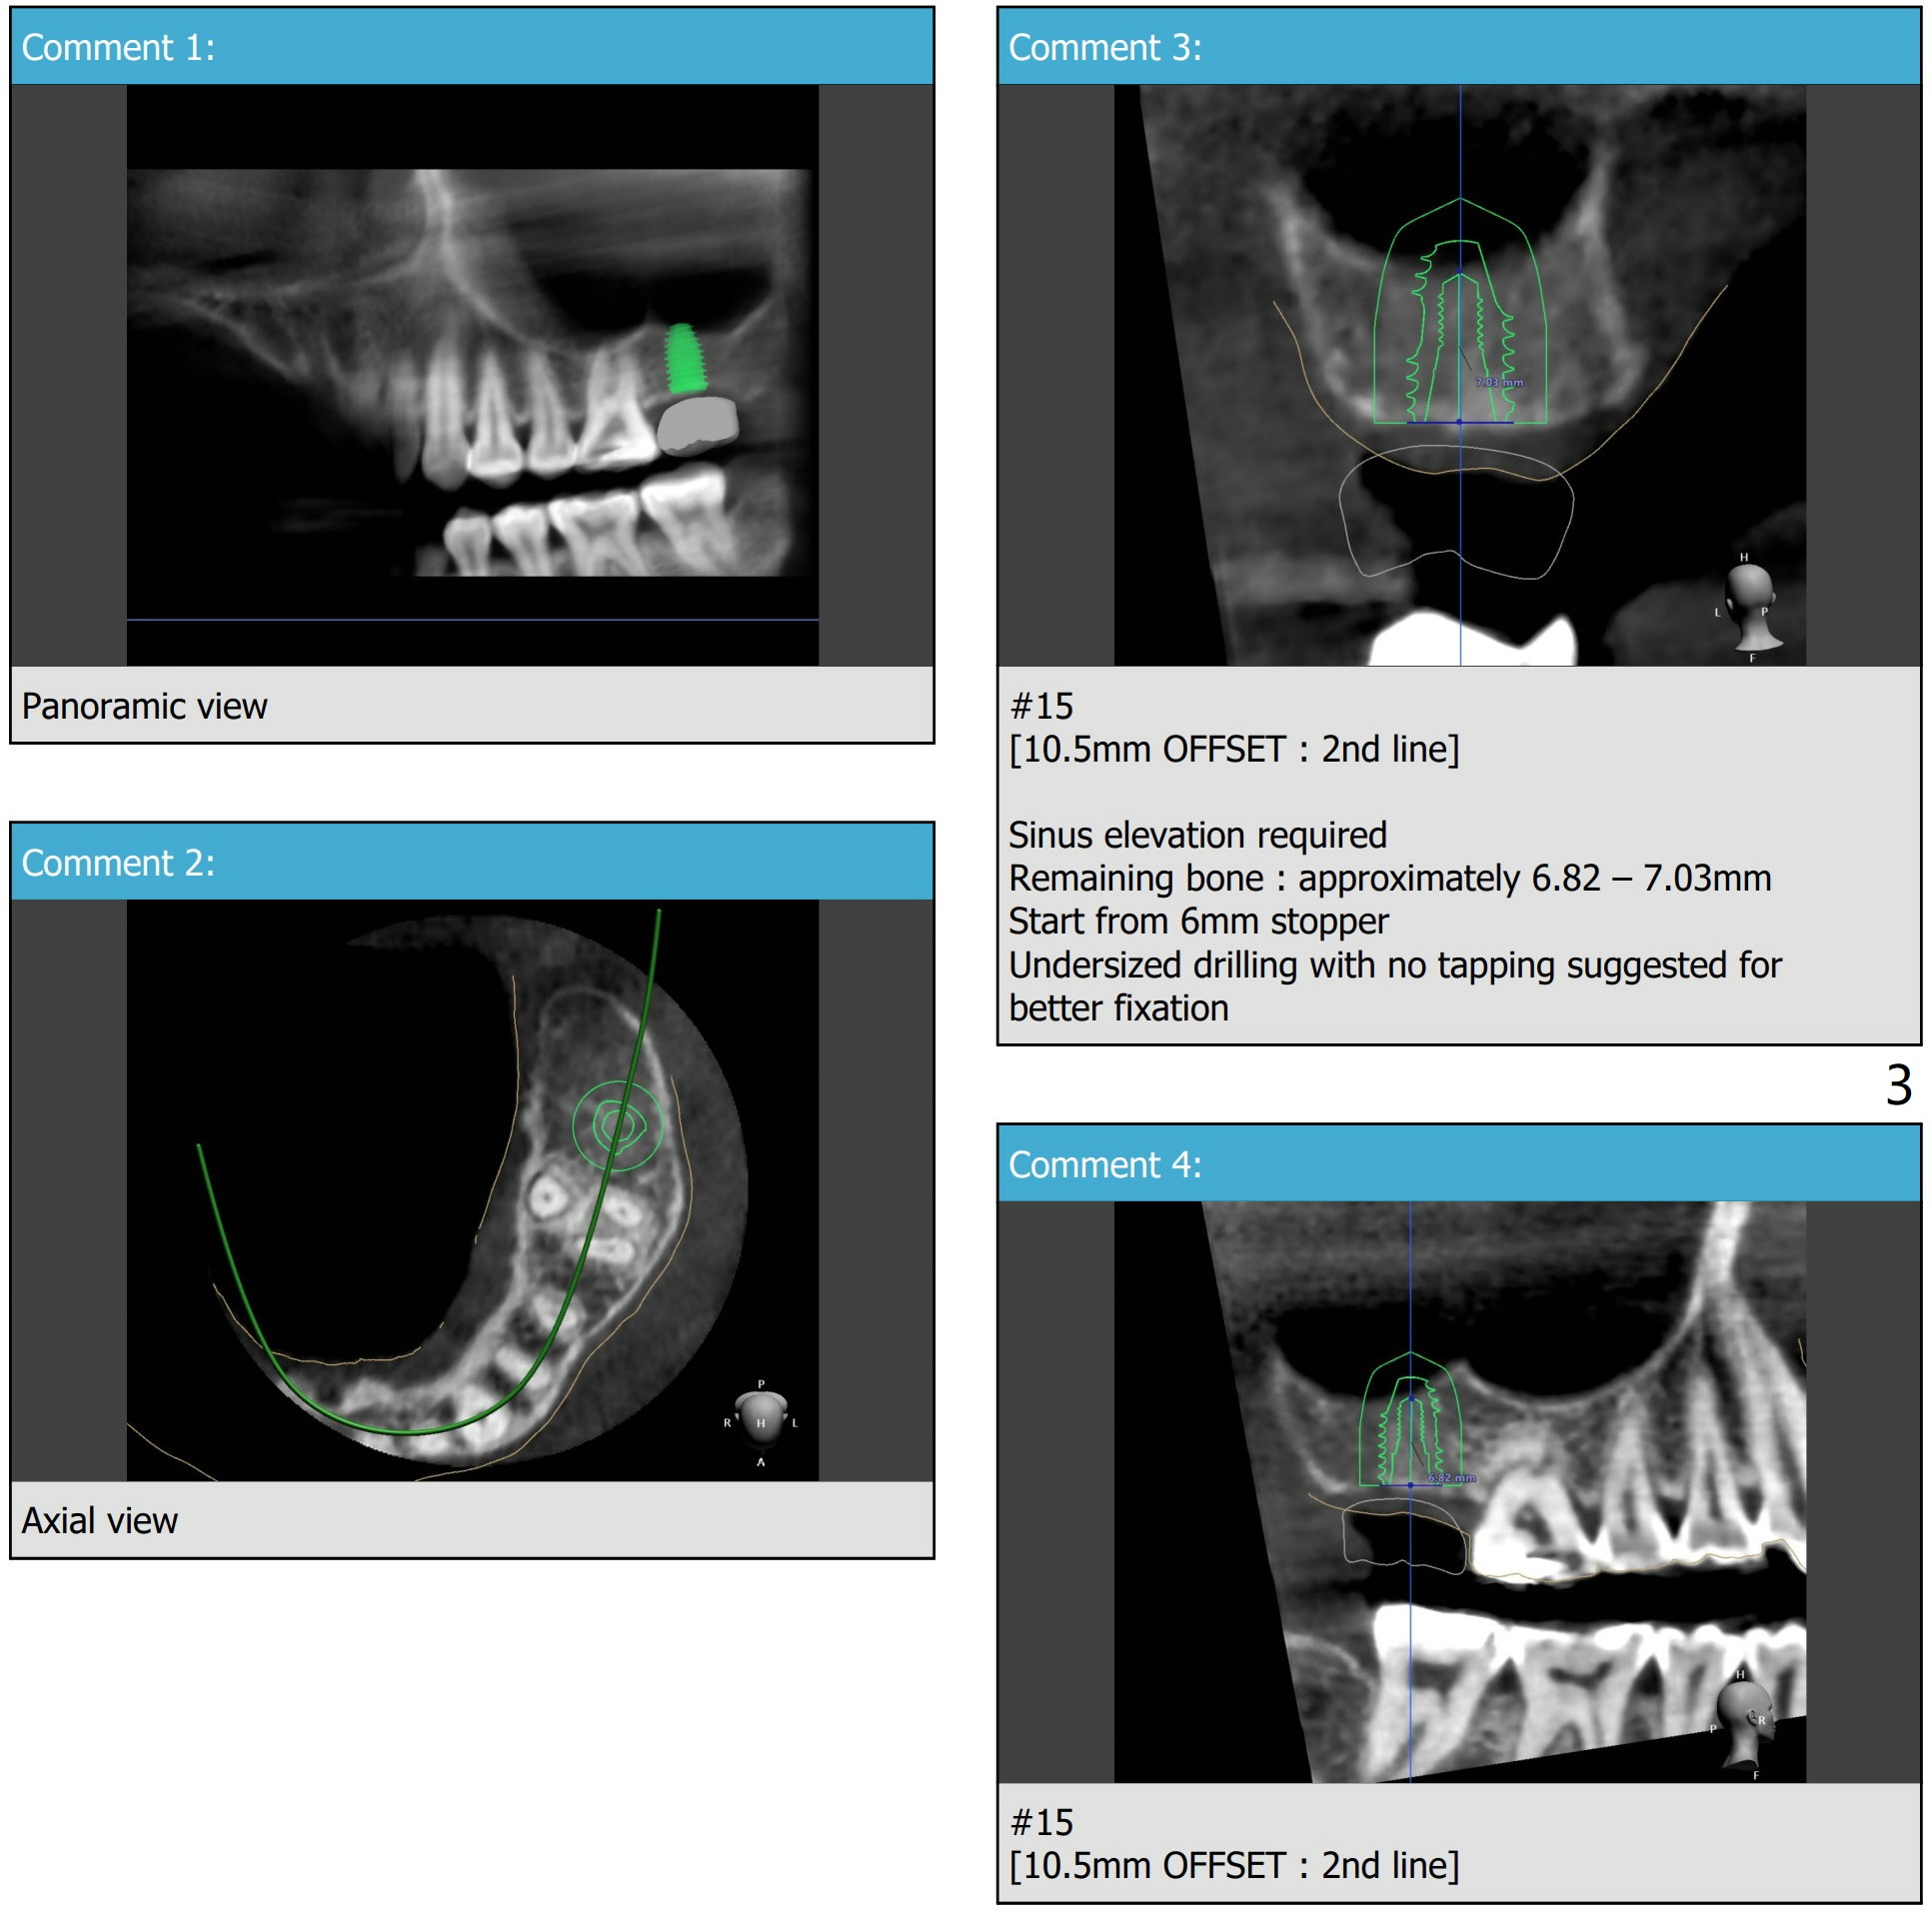

A 39-year-old woman agrees to have an implant at #15 one year post extraction without bone graft. Prepare PRFx1, 4 mm Biopsy punch and 4-0 Plain Gut suture.